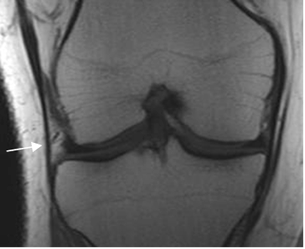

Los ligamentos colaterales unen el fémur distal, con la tibia y el peroné proximal. (Fig 20).

Fig 20. Ligamentos colaterales normales.

A y B: RM coronal en T1. LCL en A y LCM en B.

Los componentes del complejo de la esquina posterolateral, son mejor identificados en secuencias coronales y sagitales, por detrás del tendón poplíteo. (4). (Fig 21 a 28).

Fig 22. Esquina posterolateral normal.

A: RM coronal y B: RM sagital en T1. Inserción conjunta en la cabeza del peroné del LCL (Flecha delgada) y el biceps femoral (Flecha gruesa).